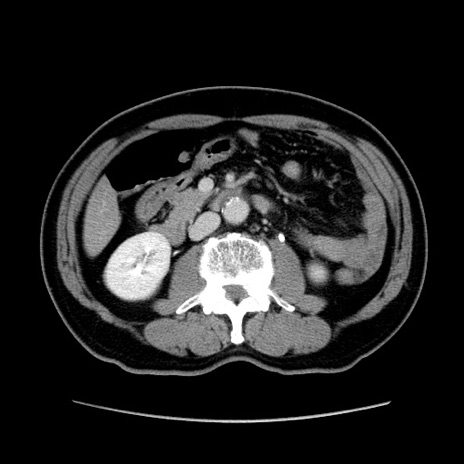

症例34(横断像)

【症例】60歳代 男性

【主訴】右鼠径部膨隆

【現病歴】1年程前より右鼠径部膨隆あり。自己にて還納可能だったため放置していた。3時間前より右鼠径部の脱出を認め、還納困難となり受診。

【既往歴】高血圧

【身体所見】右鼠径部に小児頭大の膨隆あり。弾性硬であり、用手還納は困難。左鼠径部にも膨隆を認める。脱出はなし。

【データ】WBC 15500、CRP 測定なし